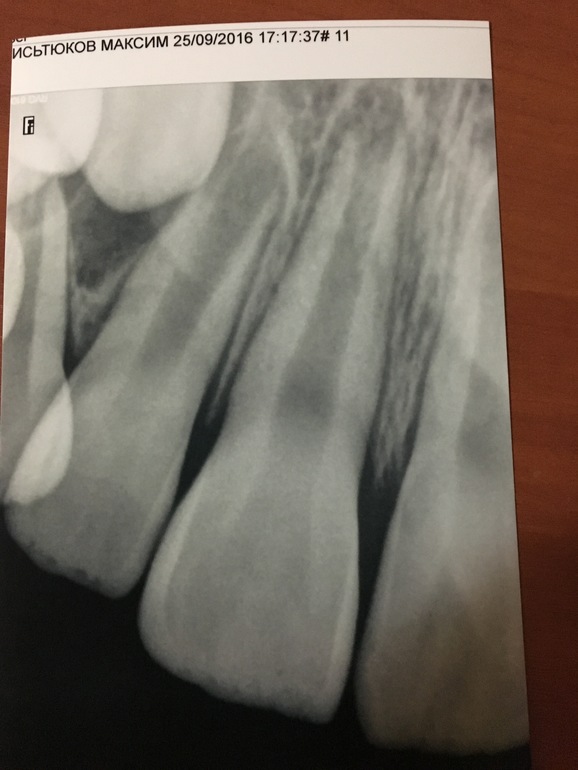

Сын 25 сентября ударился передними зубами об огрождение. Не смотря на то что он не плачет, рыдал в голос. Удар пришелся на на передний верхний зуб (центральный резец). Зуб ушел немного Внутрь, вокруг зуба, десна кровила но не сильно. Обратились к стоматологу вечером этого дня, зуб был немного подвижен, связки все разорваны. Сказали под наблюдением! Не чего этим зубом не кусать и не жевать. 2,5 нелели следовали рекомендациям. Сейчас ребенок говорит что зуб начал побаливать. Я простукиваю ему передние зубки, когда касаюсь травмированного говорит что не приятно. Неужели надо удолять нерв???? Чем это черевато в столь раннем возрасте? Нам. 8,5 лет.